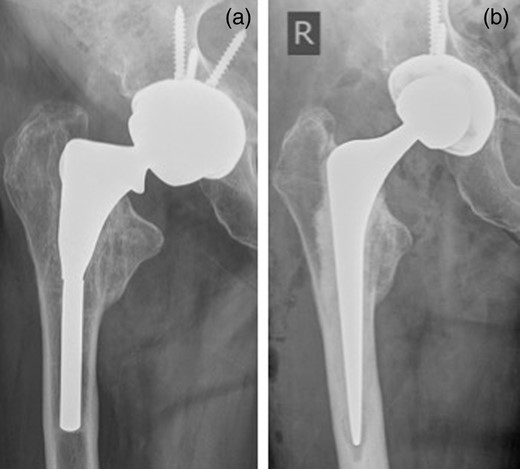

An 83-year-old female presented to our MoM for a routine review. Fourteen years previously, she had undergone a bipolar hemi-arthroplasties with a Furlong hip system (JRI limited UK). The bipolar hemi-arthroplasties was revised 6 years previously due to increasing hip pain and protrusion. At revision to THR, an R3 acetabular cup with a metal liner (Smith & Nephew, UK) was used retaining the primary stem. She described a 2-month history of a significant increase in pain over her right hip. There was no history of trauma or fall. X-rays showed a fracture through the stem of her right femoral component with radiolucent line in Zones 1, 2, 6 and 7 (Fig. 2a). She was admitted from the clinic and right hip was revised with ceramic on polyethylene bearing using Exeter stem and Trident cup (Stryker UK Limited; Fig. 2b).

(a) Fracture through the stem of right femoral component. (b) Post-revision X-ray.